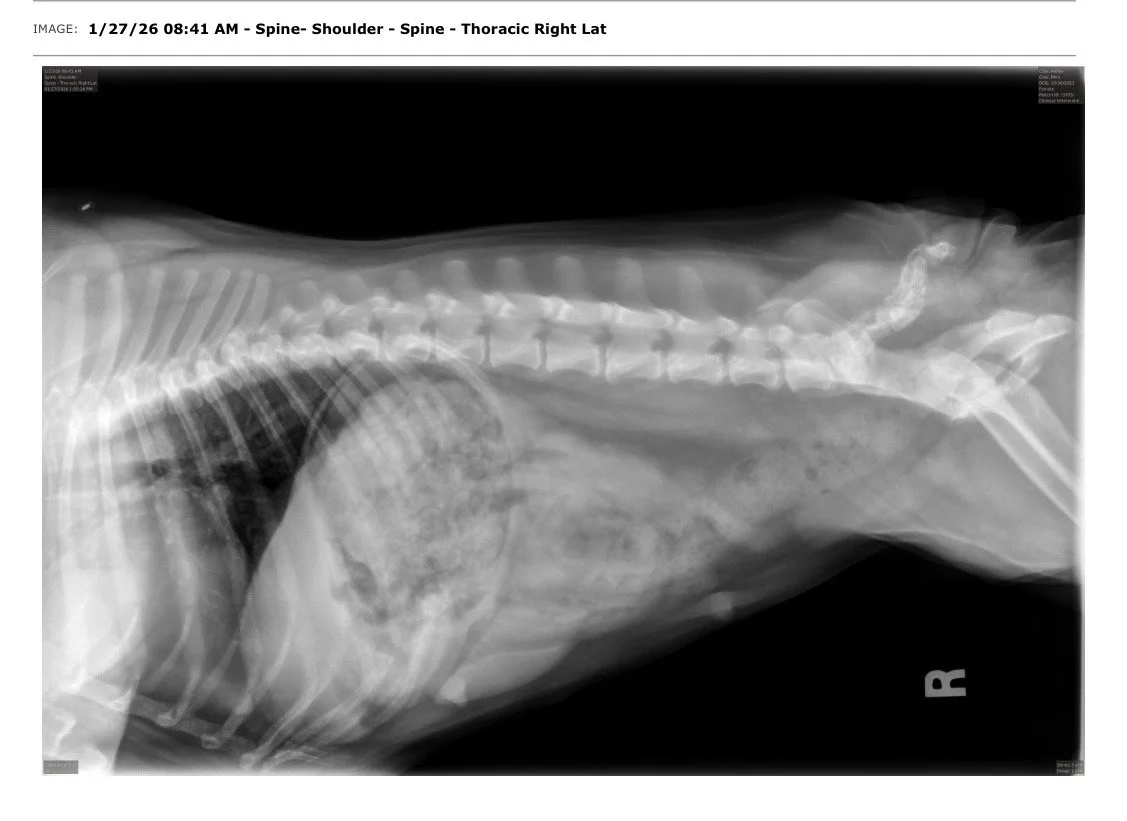

Testés OFA de la race pour Hanches, Coudes, Rotules, Colonne Vertébrale, Coeur & Yeux.